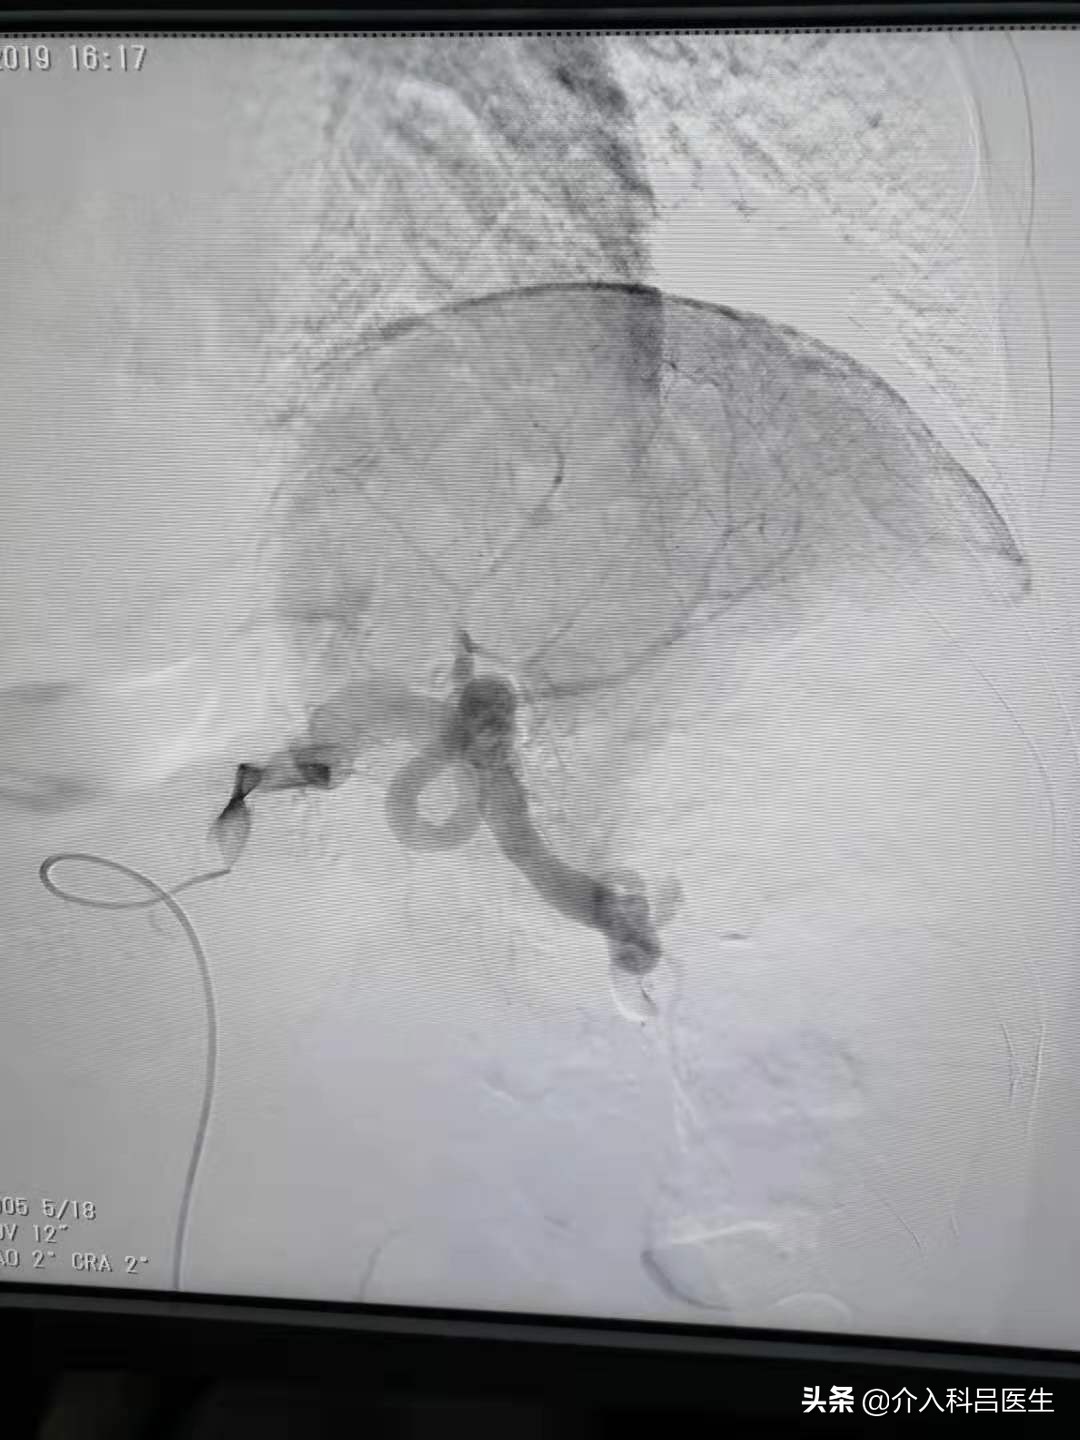

20天前复发之后,在南阳尝试做这项手术,但是没有成功,因为这项手术一难度比较大,二就是血管重新开通,还是有一点风险的,所以医生丰富的经验是非常重要的。老陈无奈又来找到我,昨天我给他了做了手术,还是比较成功的。老陈因为皮下静脉曲张,导致他肝硬化、脾功能亢进,又顺便给他的脾脏做了部分性栓塞。